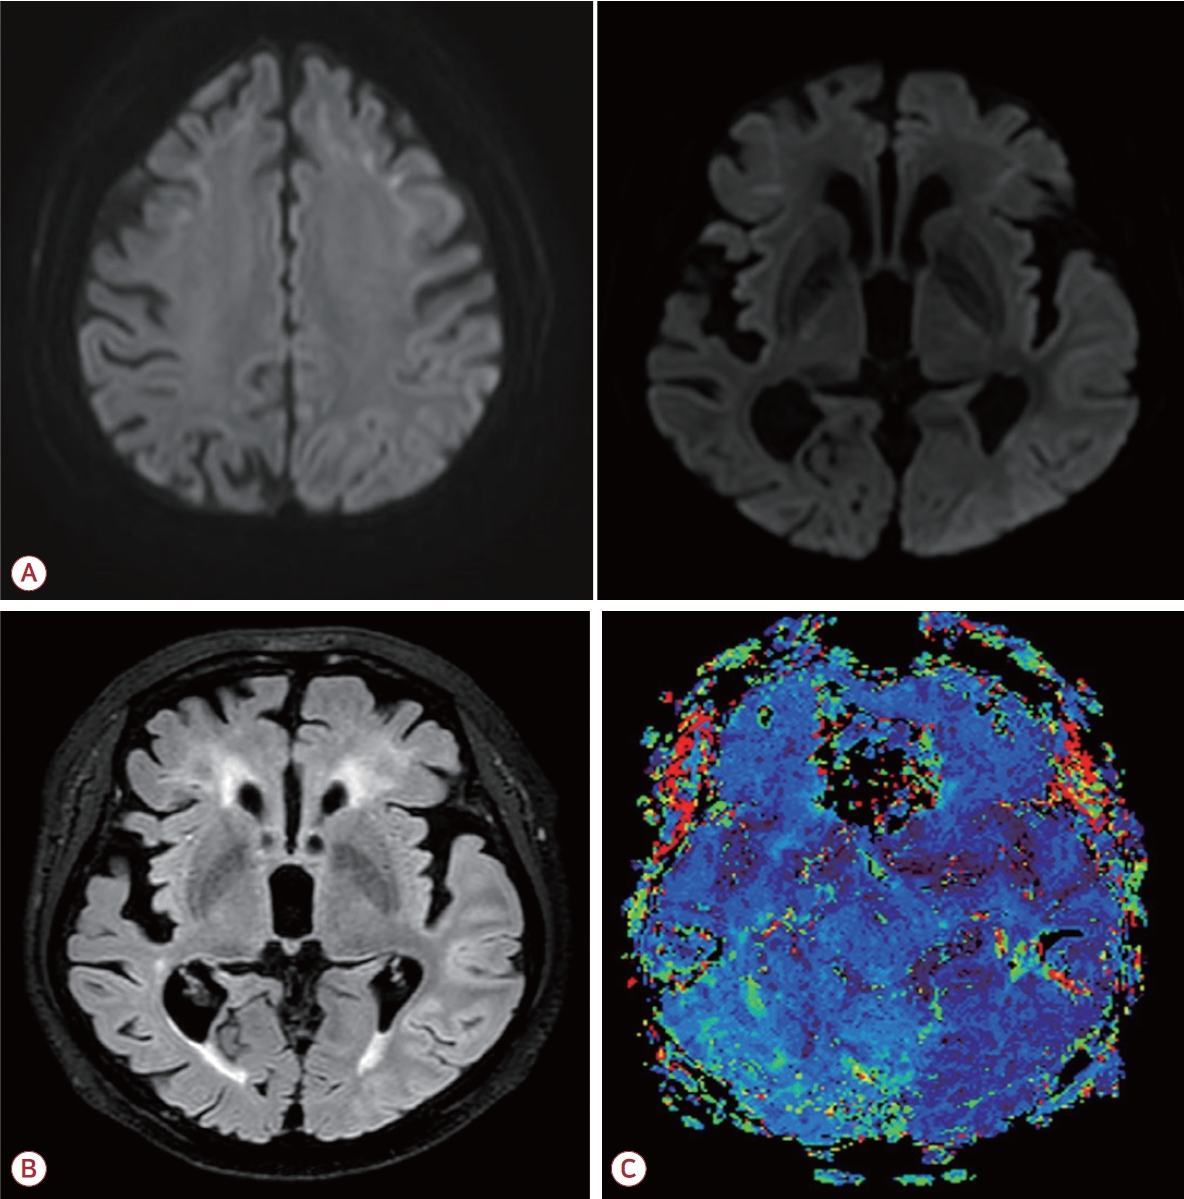

응급실에서 시행한 신경계진찰상 의식은 명료했으나 단순 명령 수행과 이름 대기 모두 불가능하였으며 “몰라”, “아파”의 발화만 반복하여 유창성도 저하되어 있는 완전실어증(global aphasia)이 확인되었다. 그 외 뇌신경 검사, 운동기능 및 감각 기능의 이상은 없었다. 갑작스러운 완전실어증으로 뇌혈관질환 등을 우선 감별하기 위해 뇌MRI를 시행하였으며 확산강조영상(diffusion weighted image, DWI)에서 양측 전두엽의 피질수질접합부(corticomedullary junction)를 따라 선형의 고신호강도가 관찰되었다(Fig. 1-A). 혈액 검사와 뇌척수액 검사는 정상이었으며 뇌척수액의 세균 및 바이러스 표지자도 모두 음성이었다. 경련 등을 감별하기 위하여 입원 후 지속 뇌파감시를 시행하였고 발작파(ictal discharge)는 나타나지 않았으나 좌측 전측두엽의 국소적 서파가 확인되었다(Fig. 1-B).

Figure 1.

Initial examination of the patient. (A) On his initial brain magnetic resonance imaging (MRI), diffusion weighted image (DWI) images showed a U-shaped high intensity lesion in bilateral frontal corticomedullary junction. (B) On continuous electroencephalography (EEG), there were no ictal discharges but focal slow waves in left fronto-temporal area. The symptom of global aphasia persisted during continuous EEG. EKG; elektrokardiogramm, EMG; electromyogram.